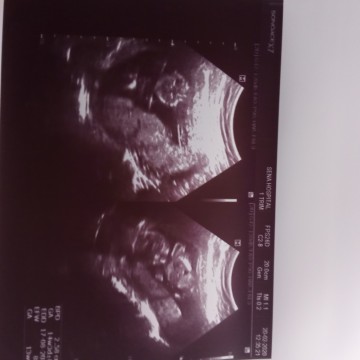

น้องอยู่ตรงไหนค่ะดูไม่ออกเลยค่ะ15w

ตรงกลมๆตรงกลางคือหัวค่ะ แล้วก็มีแขน 2 ข้างใต้หัว